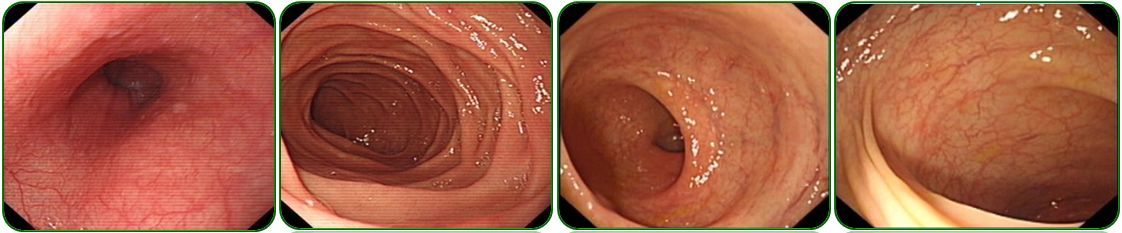

肺部及腹部CT提示右侧胸腔大量积液,右肺中下叶局限性膨胀不全、左肺上叶前段小结节影、纵隔稍肿大淋巴结、腹腔大量积液、盆腔少量积液、肝胆脾、胰腺及双肾CT平扫未见明显异常征象,如图5;

图5 胸部及腹部CT检查

肺部CT提示双肺纹理增多、左侧胸腔少量积液,如图7a-b;

腹部彩超示腹腔积液,如图7c。

图7 胸部CT及腹部彩超检查